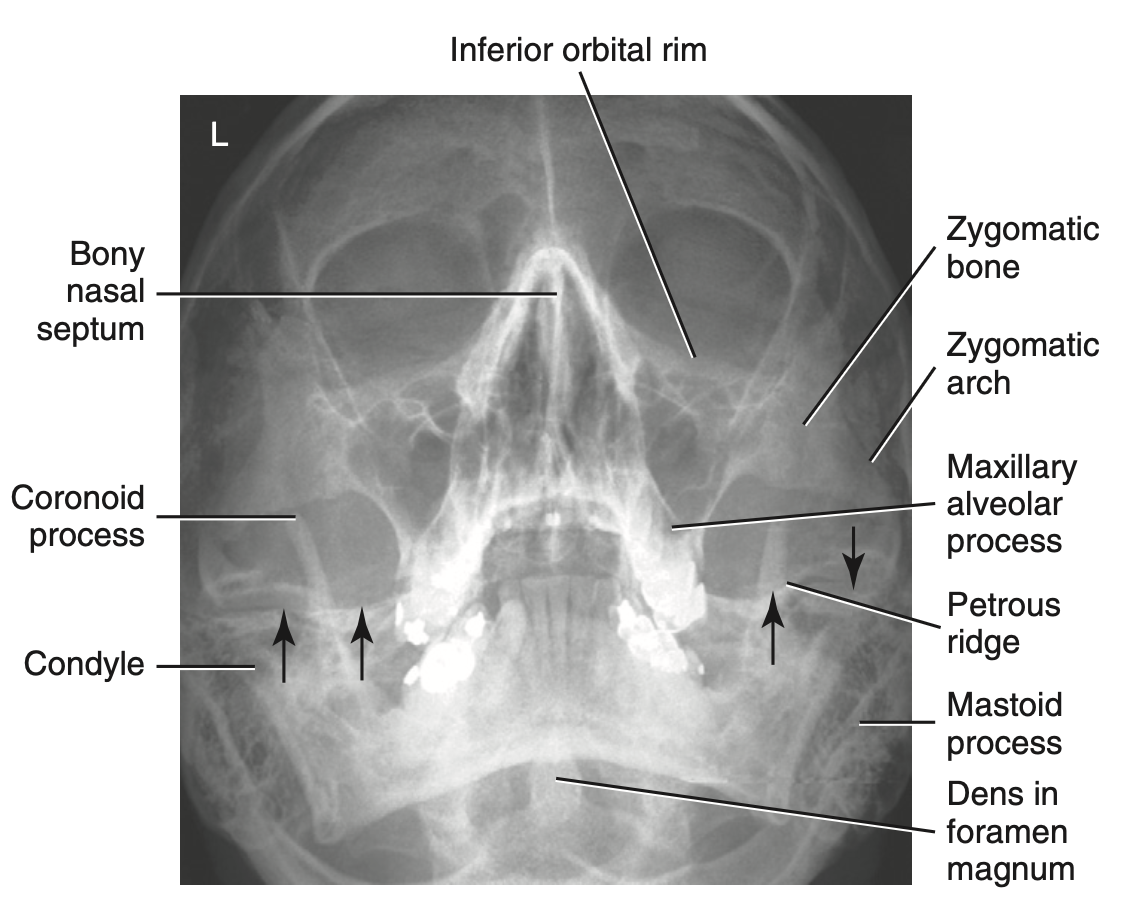

Facial bone demonstration:

Orbital rim/base, maxilla, zygoma, nasal

septum, anterior nasal spine

Facial bone critique:

Petrous pyramids are in lower 1/3 of orbits

How do you critique radiograph of PA axial projection: Caldwell method for facial bone?